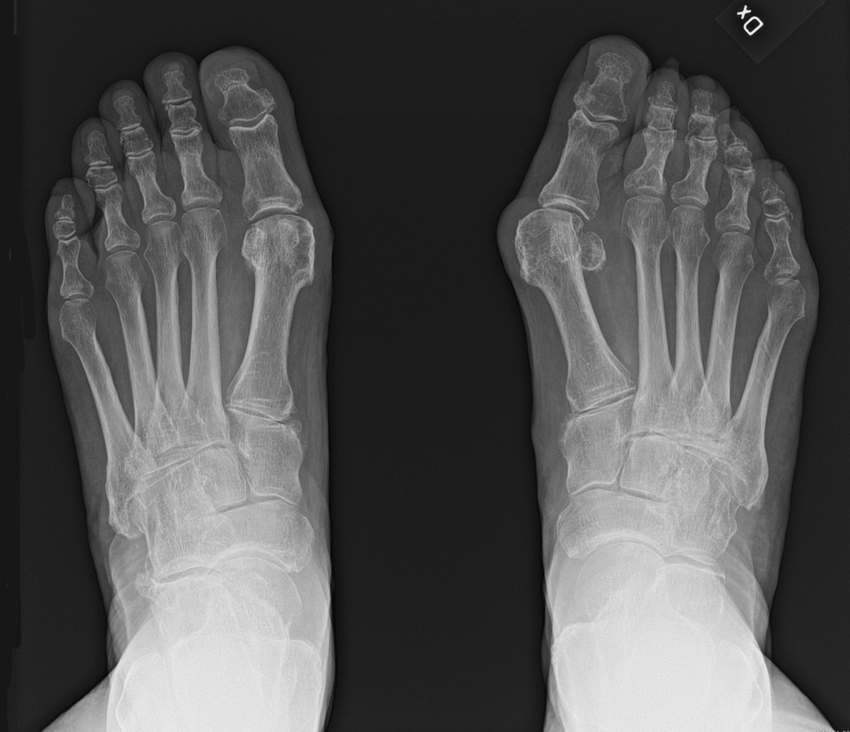

Hallux valgus karakteriseras av en felställning i metatarsofalangealled I, som kan bidra till smärta och estetiska besvär för patienten. Inte sällan påverkar felställningen valet av sko (svårt att hitta en passande sko) och gångstil.

Slätröntgen med belastning hos patient med bilateral hallux valgus. Notera mer uttalad felställning på höger sida.

• Belastad slätröntgen, alternativ datortomografi, är aktuell inför operation, för bedömning av svårighetsgraden och vinkelfelställningen samt i differentialdiagnostiskt syfte, däribland för utvärdering av eventuell artrosförekomst [26, 27].